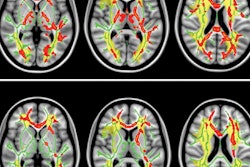

In this study, Dutch researchers compared 16 patients with early Alzheimer's disease with 17 healthy, age-matched controls. They used contrast-enhanced MRI to measure blood-brain barrier leakage rates and create a histogram to help determine the amount of the leaking brain tissue. With contrast-enhanced MRI, the researchers could detect early microvascular changes in those with Alzheimer's disease, even when no directly visible cerebrovascular abnormalities were seen.

The rate of blood-brain barrier leakage was significantly greater in Alzheimer's patients than healthy controls, lead author Harm van de Haar and colleagues reported. Alzheimer's patients also had a significantly higher percentage of leaking brain tissue in the gray matter, including the cortex.

The researchers also found a relationship between the extent of blood-brain barrier impairment and decline in cognitive performance, suggesting that a compromised blood-brain barrier is part of the early pathology of Alzheimer's.